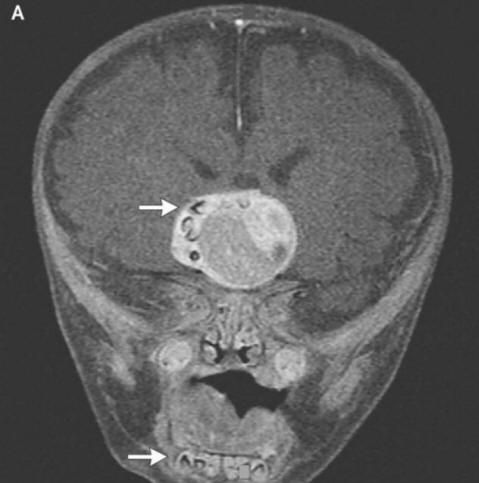

Hirurzi iz američke države Merilend morali su ga provesti najtežih operacija u njihovoj praksi. Roditelji četiri meseca dečki su oglasili uzbunu i posle otišli doktorima primijetili da im glava djeteta raste prebrzo. Ljekari obavili pregled i ustanovili da mu je zub porastao u mozgu pacijenta.

Fotografija iz otvorenih izvora Kako su uplašeni roditelji objasnili hirurzi i onkologa je to zbog formiranja rijetke urođene tumori – kraniofariniomi, piše New England Journal of Medicine. Ova neoplazma u velikoj većini slučajeva benigna, međutim, može narasti do veličine lopte golf i uzrokuje smanjenje osjećaja mirisa, oštećenje sluha i vida i povećava i intrakranijalni pritisak. Istraživači uvijek sumnja da su se ovi tumori koji se pojavljuju kod djeteta već ranije trudnoća, nastala iz istih ćelija kao i zubi, otkad su otkrili velika nakupljanja kalcijuma, ali pravi formirani zub prije ovog slučaja koji ne mogu pronaći računati.

Hirurzi su uspješno uklonili fotografiju iz otvorenih izvora Tumor, dečko, rekli su, ide dobro. Međutim zub koji odrastao mu je hipofiza, a opet je poremetio mozak, pravilna proizvodnja hormona – pacijent će ih morati ranije uzimati kraj života. Ovaj slučaj s pravom može zauzeti svoje mjesto popis najčudnijih operacija koje obavljaju onkolozi. U međuvremenu u mladić iz Irana, koji je morao liječite dlakave oči. Čudan mu se tumor u oku gotovo pojavio odmah po rođenju, međutim s dobi od 19 godina znatno se povećala u veličine (do 0,6 cm) i sprečavali zatvaranje kapka, osim toga, od njega ukočena kosa je počela rasti. Ljekari su mu uklonili tumor i to otkrili ovo je limbalni dermoid – izuzetno rijetko, obično benigne edukacije. Prema riječima ljekara u tom slučaju je ako je mladić nastavio da se povlači s lijekovima, njegova oteklina ne samo da može rasti kosu, već se i početi znojiti: s vremenom na neoplazmi se često pojavljuju odgovarajuće žlijezde.